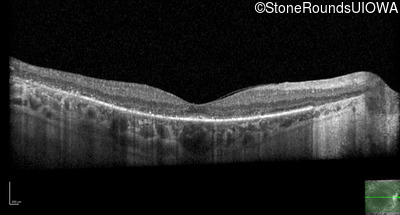

Optical Coherence Tomography - Right - 20/40 -1

Exemplar / OCT Stack

Optical Coherence Tomography - Left - 10/120 -1